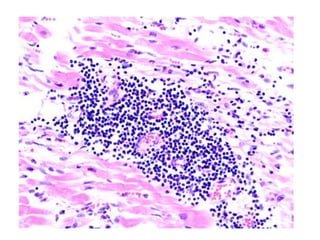

• En esta caso hay inflamación de

miofibrillas, , autoanticuerpos e infiltrado

inflamatorio crónico.

• La biopsia endomiocardica por

cateterismo.